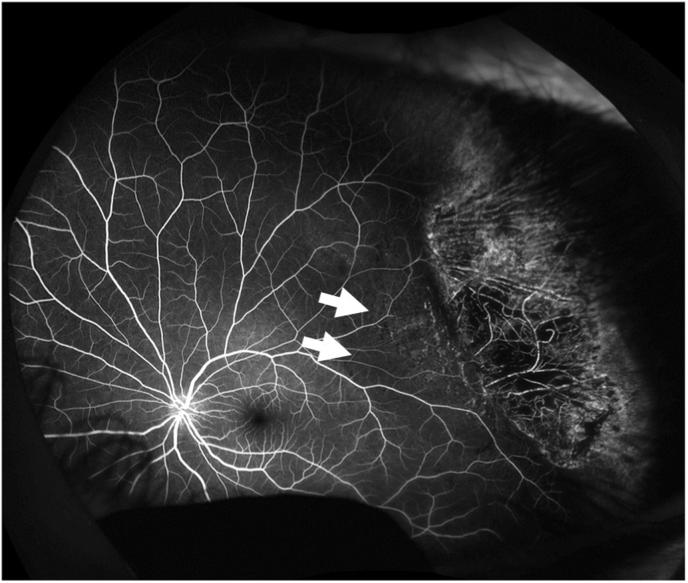

An 18-year-old Japanese man presented with traumatic retinal detachment and CR in his left eye, which had been hit by a handball. Fundus examination revealed peripheral retinal tear extending from the 1 to 3 o'clock position with retinal detachment, and CR near the area of tear. Fluorescein angiography (FA) confirmed an ischemic area near the retinal tear area at the CR. The patient underwent successful scleral buckling and cryopexy. Sequential OCTA imaging was performed and we were able to determine perfusion in the CR area, with maintained blood flow.

In blunt eye trauma, peripheral commotio retinae can be assessed non-invasively over time using OCTA. OCTA is a useful method for evaluating peripheral retinal whitened areas.